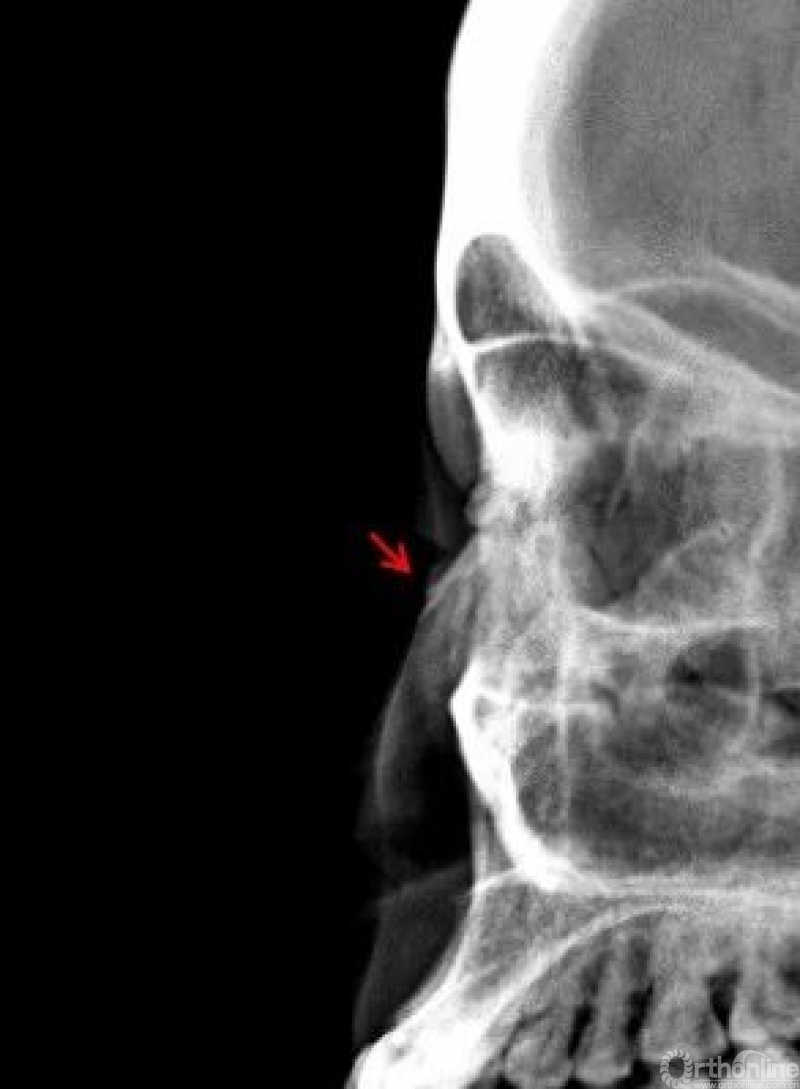

鼻骨

两个病例均显示:鼻骨中远段骨质连续中断,断端向内下方移位。鼻骨骨折

Warmreminder:鼻部受伤,有时鼻骨骨折不能做出诊断。小妙招鼻骨双侧位更容易观察